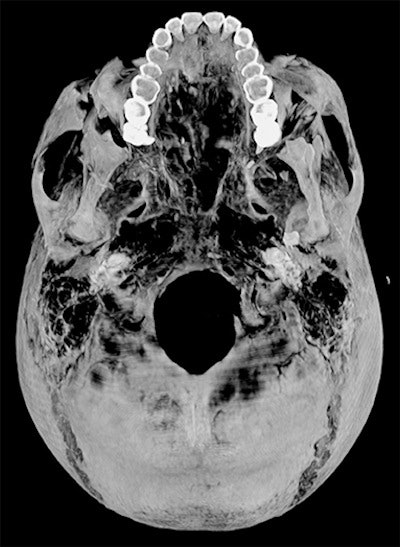

Dr. Sahar Saleem, a professor of radiology at Cairo University who specializes in CT mummy imaging, and archeologist Zahi Hawass, PhD, have used CT scans and 3D reconstructions to suggest he had multiple killers. They have presented their findings in an article published on 17 February in Frontiers of Medicine that received over 10,500 page views by February 21.

CT revealed details of the head injuries, including wounds that had not been discovered in previous examinations and had been skillfully hidden by the embalmers. The mummy's deformed hands indicate that Seqenenre may have been captured on the battlefield, and his hands were tied behind his back, preventing him from deflecting the fierce attack on his head.

The CT scans, combined with other evidence, suggest the execution was carried out by multiple attackers, which the scientists confirmed by studying five different Hyksos weapons that matched the king's wounds. The study also determined that Seqenenre was about 40 when he died, based on the detailed morphology revealed in the images, providing the most precise estimate to date, according to the authors.

In addition, the investigation revealed details about the mummification of Seqenenre's body. For instance, the embalmers used a sophisticated method to hide the king's head wounds under a layer of embalming material that functioned similarly to the fillers used in modern plastic surgery. This would imply that mummification took place in a real mummification laboratory rather than in a poorly equipped place, as previously interpreted.

Saleem examined the mummy on May 4, 2019. She said she used the usual optimum CT scan parameters, including field-of-view and slice thickness, to provide the best 3D reconstruction. Because of the COVID-19 pandemic, it took several weeks to study the Hyksos weapons stored at the Cairo Egyptian Museum and to correlate them with the injuries by physical inspection of the mummy and on CT scans.